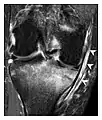

a

b

c

Figure 8: Proximal diaphyseal fatigue fracture of the tibia in a 20-year-old man with a history of regular jogging. (a) Lateral radiograph shows no obvious fracture lines but a subtle localized medial tibial cortex periosteal reaction (arrows). (b) Sagittal reformatted CT image acquired 1-month after the radiograph shows a linear hypoattenuation in the tibial cortex (arrowhead), as well as obvious periosteal thickening (arrows). (c) Sagittal T2-weighted fat-saturated image acquired the same day shows an area of hyperintensity spreading over the proximal tibia (arrows), which is consistent with the presence of proximal tibial fracture.[1]